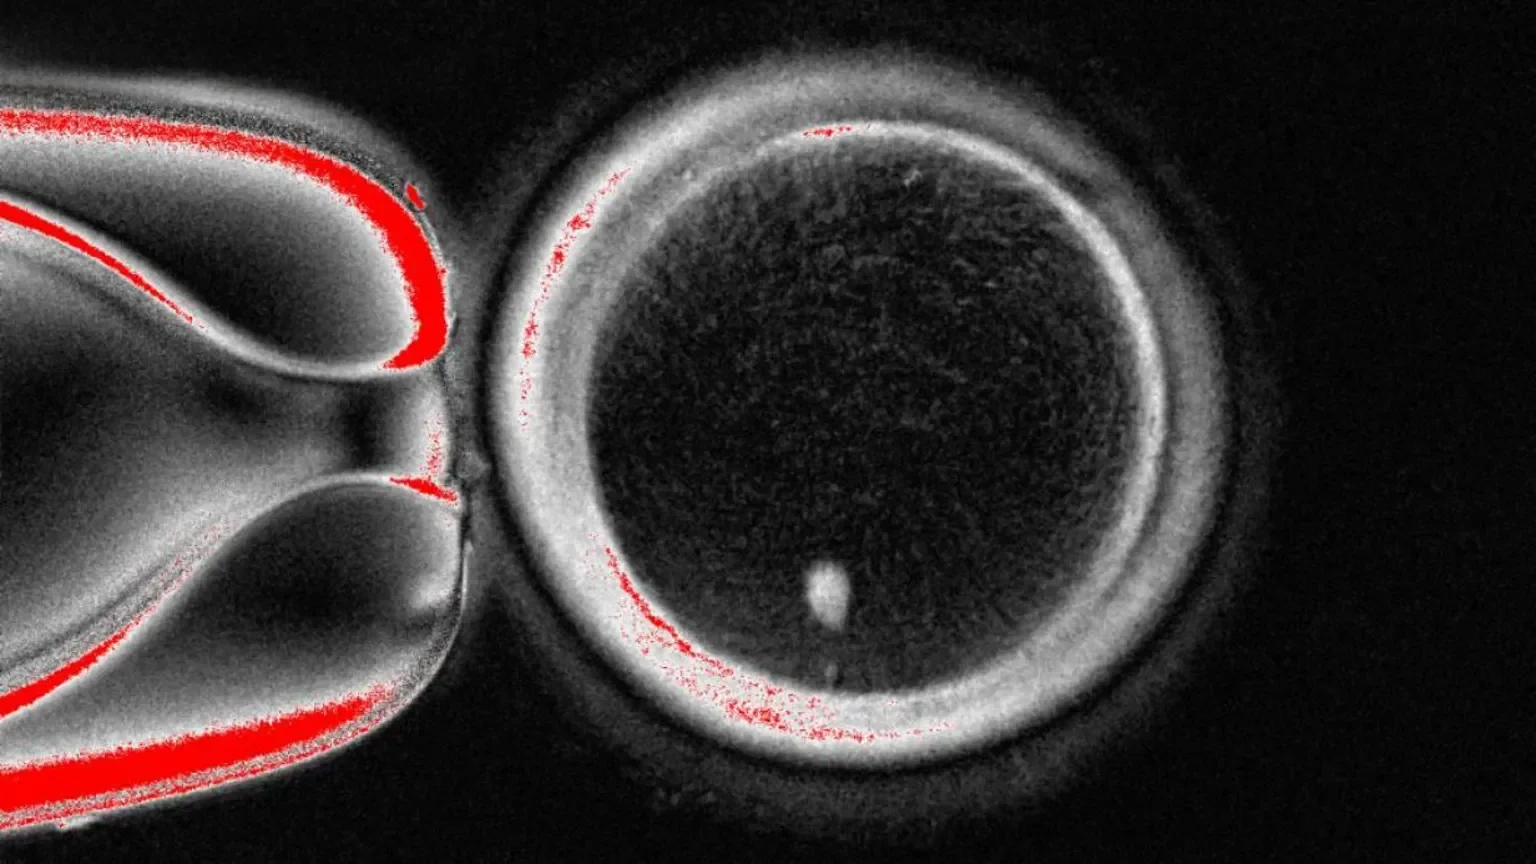

Oreqon Sağlamlıq və Elm Universitetinin tədqiqat qrupu dəridən götürülmüş hüceyrənin nüvəsini – bədənin qurulması üçün lazım olan bütün genetik kodun surətini çıxarır.

Sonra bu nüvə genetik göstərişləri çıxarılmış donor yumurtasına yerləşdirilir.

Hazırda bu texnika 1996-cı ildə dünyada ilk klonlanmış məməli olan Dolly qoyununu yaratmaq üçün istifadə olunan metodla oxşardır.

Ancaq bu yumurta artıq mayalanmaq üçün hazır deyil, çünki o artıq tam xromosom dəstinə sahibdir.

Siz valideynlərinizdən hər birindən 23 xromosom alırsınız, ümumilikdə 46 xromosomunuz olur və yumurta da artıq bu xromosomlara malikdir.

Növbəti mərhələ isə yumurtanı xromosomlarının yarısını atmağa inandırmaqdır. Tədqiqatçılar bu prosesə “mitomeyoz” adını veriblər (söz mitoz və meyoz – hüceyrələrin bölünmə üsulları – sözlərinin birləşməsidir).